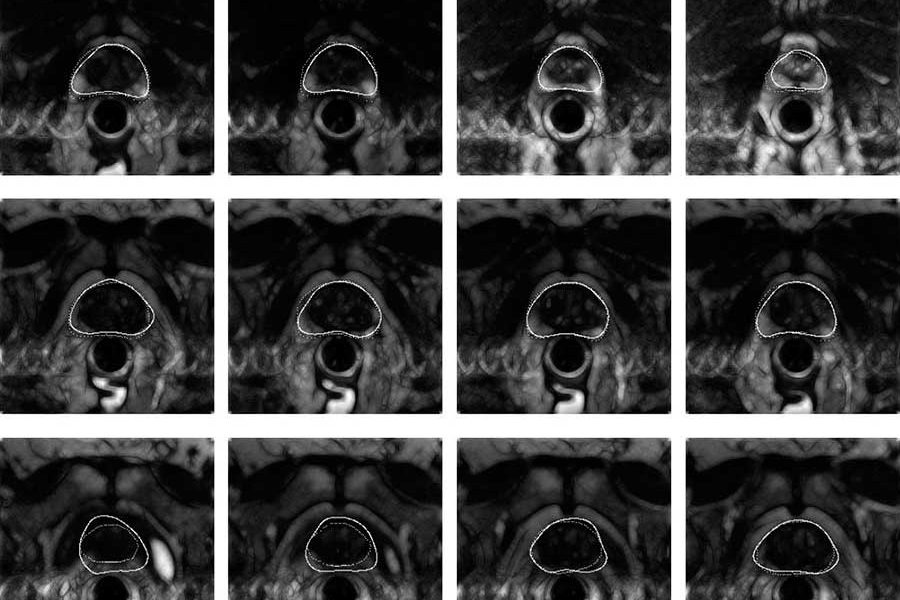

- трансректальное УЗИ предстательной железы.